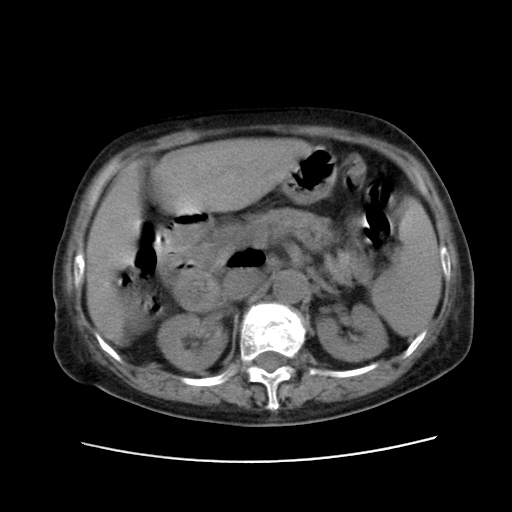

女,77.无不适

肝脏变异、异位胆囊,肝右叶肝内胆管结石并肝内胆管扩张。

肝右叶肝内胆管结石并肝内胆管扩张。

肝右叶肝内胆管结石并肝内胆管扩张。胆总管下段梗阻,考虑壶腹部占位。

右侧肝内胆管局限性扩张,其内密度不均匀,扩张的胆管壁增厚,考虑肝内胆管炎合并结石可能性大